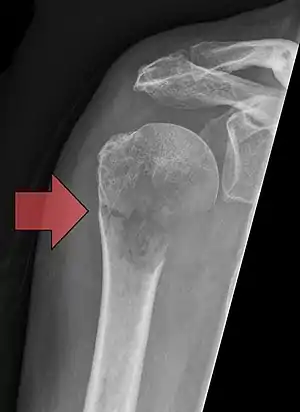

| Pathological fracture of the humerus in a patient with metastasis of renal cell carcinoma | |

Pathological fractures present as a chalkstick fracture in long bones, and appear as a transverse fractures nearly 90 degrees to the long axis of the bone. In a pathological compression fracture of a spinal vertebra fractures will commonly appear to collapse the entire body of vertebra.